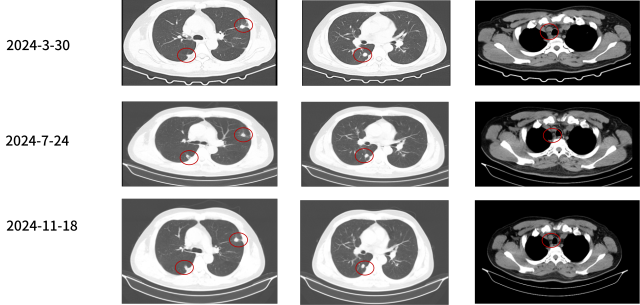

2024-04-

三线:伏罗尼布+依维莫司

脑转移的治疗

2024-04-至今

脑转移放疗

治疗结局:影像学评估 SD

治疗结局:脑转移评估 强化灶消失